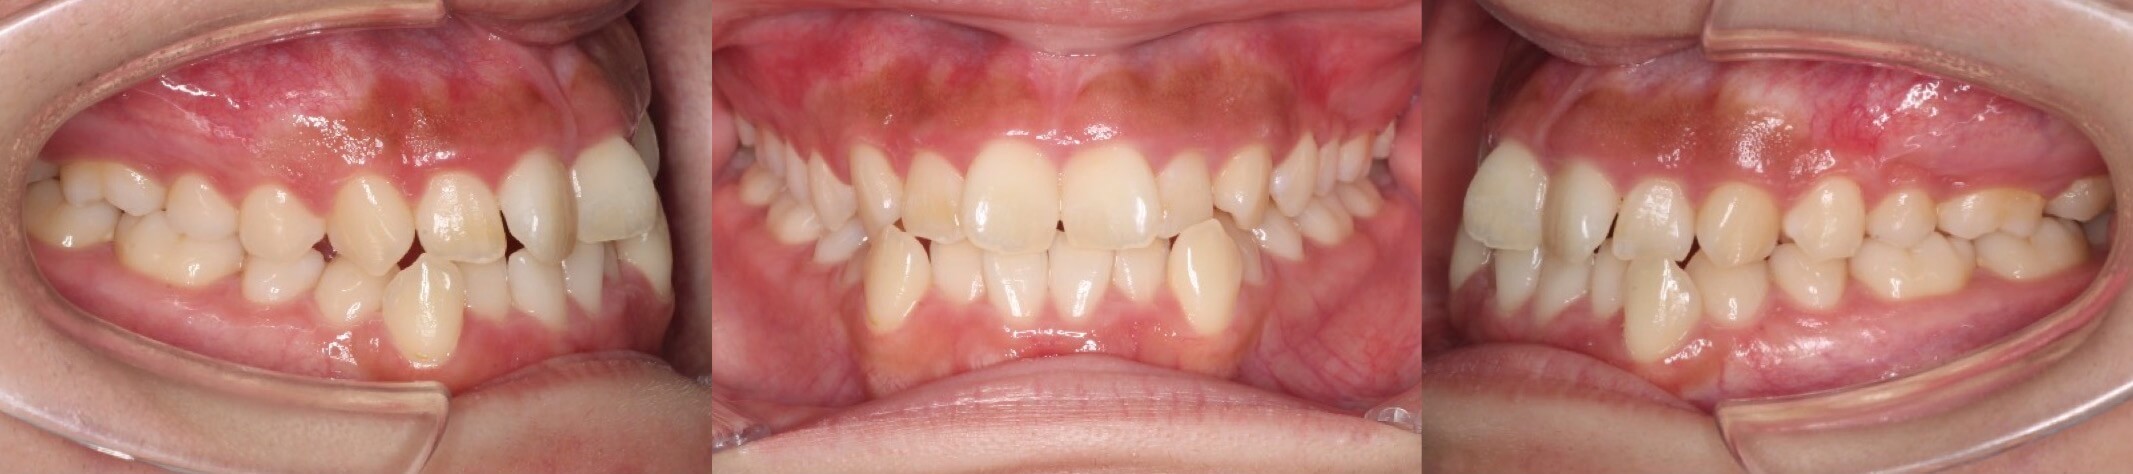

高校生女子・唇側矯正装置アンカースクリュー

<顔のビフォーアフター>

<症例概要>

主訴:でこぼこ

年齢・性別:高校生女子

住まい:千葉県八千代市

症状:著しい叢生

治療方針:上顎歯列後方移動・上下顎歯列拡大・ストリッピング

治療装置:唇側矯正装置

固定装置:歯科矯正用アンカースクリュー(口蓋側壁x2)・上下ポーター型拡大装置

抜歯:なし

治療期間:2年1か月

リテーナー:上下プレートタイプ+クリアタイプ下・フィックスタイプ

治療費用:968,000(税込)

代表的副作用:痛み・治療後の後戻り・歯根吸収・歯髄壊死・歯肉退縮

▶︎その他の副作用

著しいスペース不足による、上下顎歯列全体のデコボコです。アンカースクリューから上の奥歯を後方移動させ、歯に少しヤスリをかけて小さくするストリッピングを併用し、前歯を前に出すことなく矯正を完了する事ができました。治療後は素敵な笑顔になりました。